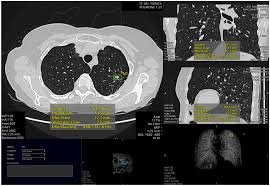

ParagonCare Partners with Coreline Soft to Advance AI-Powered Lung Cancer Screening in Australia

Strategic collaboration introduces Coreline Soft’s AI-driven imaging solutions to enhance early lung cancer detection, supporting the National Lung Cancer Screening Program (NLCSP) in Australia....